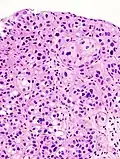

The 1973 WHO grading system for transitional cell carcinomas (papilloma, G1, G2 or G3) is most commonly used despite being superseded by the 2004 WHO[14] grading for papillary types (papillary neoplasm of low malignant potential [PNLMP], low grade, and high grade papillary carcinoma). High-grade carcinoma typically displays more pleomorphism, multiple mitoses, euchromatin and relatively prominent nucleoli, and uneven distribution of nuclei.

Histopathology of urothelial carcinoma of the urinary bladder, showing a nested pattern of invasion. Transurethral biopsy. H&E stain -

Histopathology of urothelial carcinoma of the urinary bladder. -